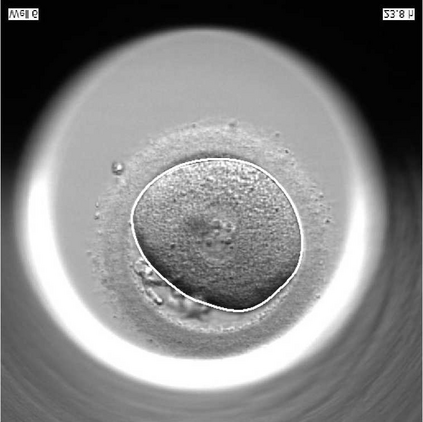

We present a novel method for identification of the boundary of embryonic cells (blastomeres) in Hoffman Modulation Contrast (HMC) microscopic images that are taken between day one to day three. Identification of boundaries of blastomeres is a challenging task, especially in the cases containing four or more cells. This is because these cells are bundled up tightly inside an embryo's membrane and any 2D image projection of such 3D embryo includes cell overlaps, occlusions, and projection ambiguities. Moreover, human embryos include fragmentation, which does not conform to any specific patterns or shape. Here we developed a model-based iterative approach, in which blastomeres are modeled as ellipses that conform to the local image features, such as edges and normals. In an iterative process, each image feature contributes only to one candidate and is removed upon being associated to a model candidate. We have tested the proposed algorithm on an image dataset comprising of 468 human embryos obtained from different sources. An overall Precision, Sensitivity and Overall Quality (OQ) of 92%, 88% and 83% are achieved.